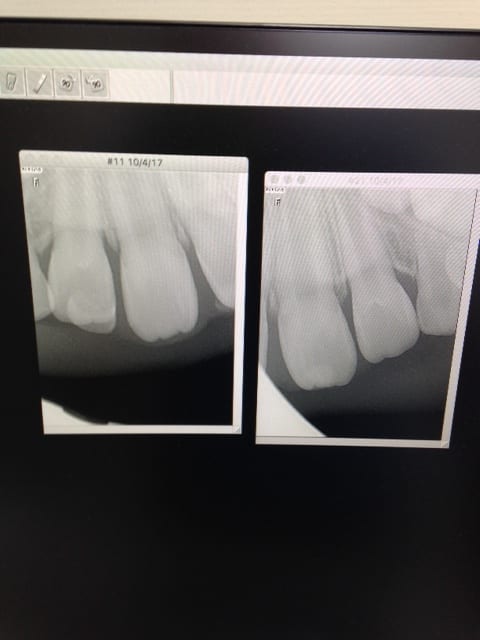

J ai reçu hier au cabinet cette petite fille de 7,5 ans, les incisive sup ne font pas leur éruption

Ca finira effectivement par se régler tout seul, mais si la gamine ressent une gêne, j'y mettrais bien un coup de lame 15 pour décomprimer un peu tout ça, les incisives ont presque fini leur éruption du point de vue osseux et semblent avoir du mal à "percer".

D'autant que l'hygiène moyenne n'est peut-être qu'une conséquence de cette gencive inflammatoire.

A quel age et pour quelle raison a t elle perdu ses lacteales ??.... ca sent pas l exfoliation naturelle ;)